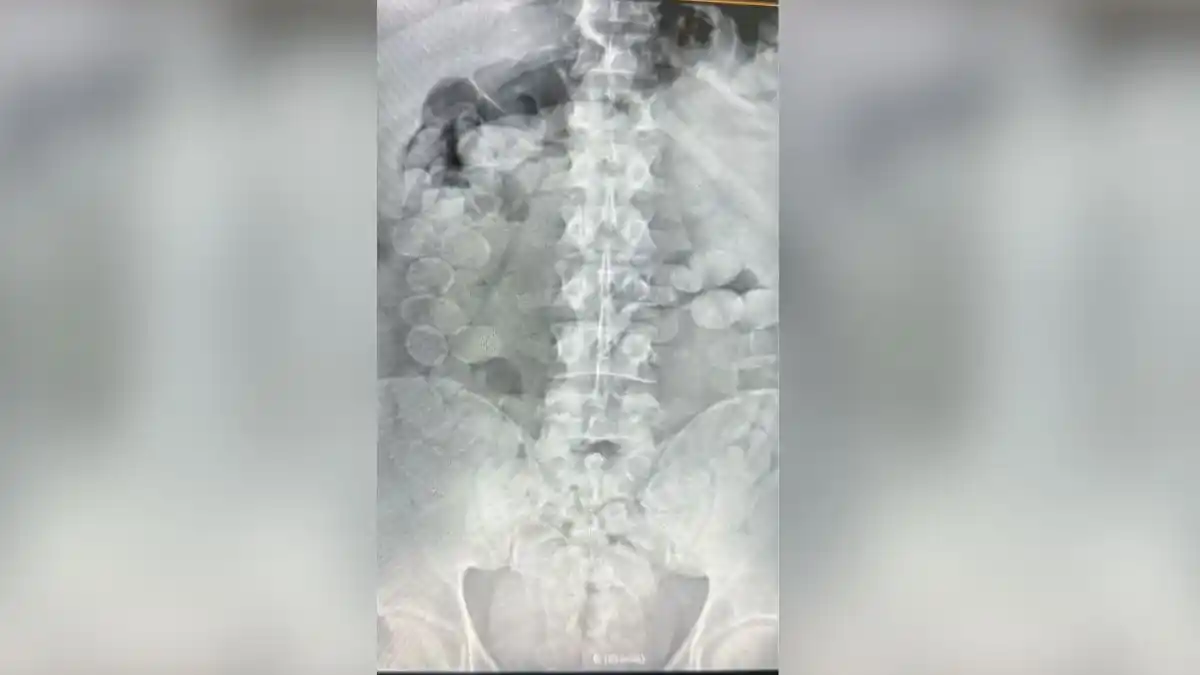

Según confirmó el fiscal federal Gustavo Onel, los sospechosos comenzaron a manifestar descompostura, motivo por el cual fueron trasladados al hospital de Ceres. Allí se les realizaron placas radiográficas, que permitieron confirmar la sospecha: cada uno llevaba entre 80 y 90 cápsulas de cocaína en el interior de su cuerpo, superando el kilo de droga por persona.

El procedimiento de evacuación se realizó bajo estricto control médico, debido al riesgo extremo que implica la ruptura de una cápsula dentro del organismo, situación que puede ser mortal.